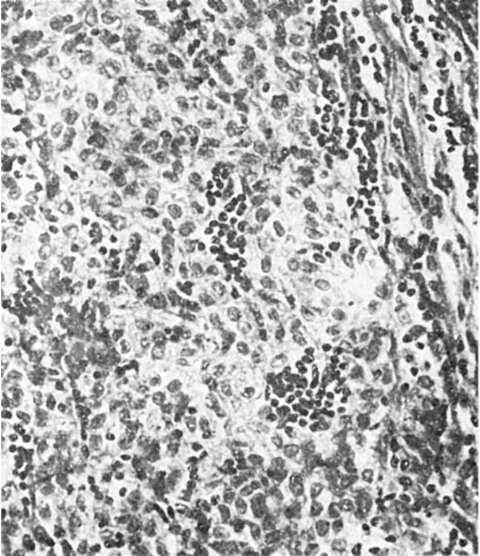

Морфологически различают 4 вида тимом (Мullег-Hermelink H., 1986). Кортикальноклеточная тимомаразвивается из кортикального эпителия, а также из клеток тимических телец, построена из крупных полигональных клеток с округлыми светлыми ядрами. Опухоль часто злокачественная (рис. 114).

Рис.

114. Злокачественная кортикальноклеточная тимома с минимальным количеством лимфоцитов